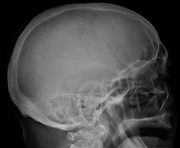

Skull X-ray showing multiple lucencies due to multiple myeloma